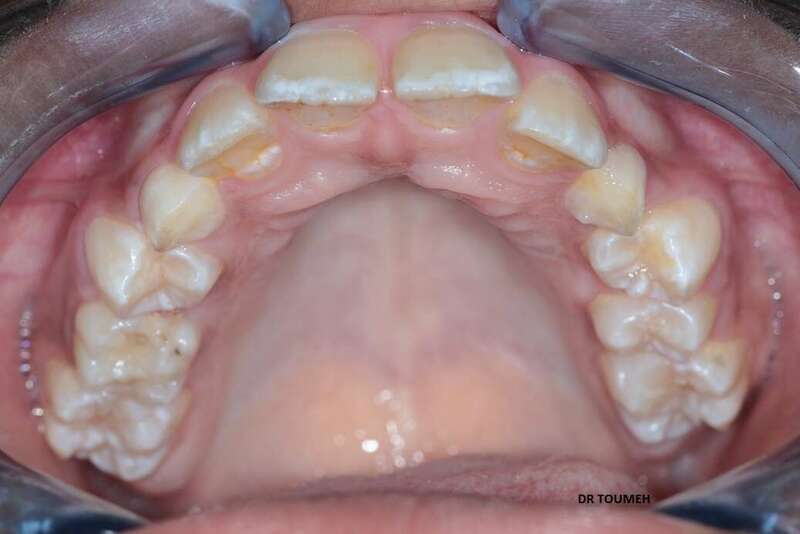

Le traitement Orthodontique doit commencer au bon moment le plutôt possible,

Avant

Votre Orthodontiste détermine le moment où il faut entamer le traitement orthodontique selon plusieurs paramétres (l'age de l'enfant, l'age osseux, le cas et le plan de traitement .....).